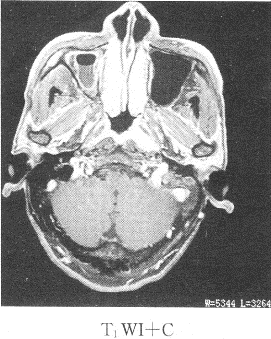

患者男性,39歲,因耳鳴,聽力下降來院,影像學(xué)檢查如圖所示

1.該患者最有可能的診斷是

正確答案:1.C;2.B;3.ABDE 解題思路:鼻咽癌我國以廣東省為高發(fā)地區(qū),男性多于女性,好發(fā)于鼻咽頂壁,其次為側(cè)壁,前壁和底壁極少。